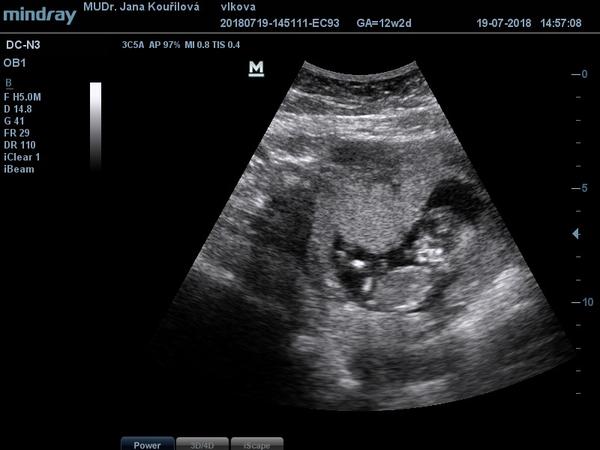

@hribek čárka je krásná!!!! Ty se cítíš jak? Já po tom druhém pokusu jsem se od začátku cítila úplně jinak, že jakoby jsem vnitřně cítila, že to bude ok. ve čt jsem byla na kontrole, 12+2, mimčo si tam hovělo s opřenýma nožičkama, pak paleček v puse...krása. Ve středu jdu na screening, tak snad bude taky vše ok. Pak začnu přemýšlet, kdy to řeknu v práci

@crazy_girl3 krasny fotecky

@luciebx děkuju 🙂 už to vypadá jako miminko ❤